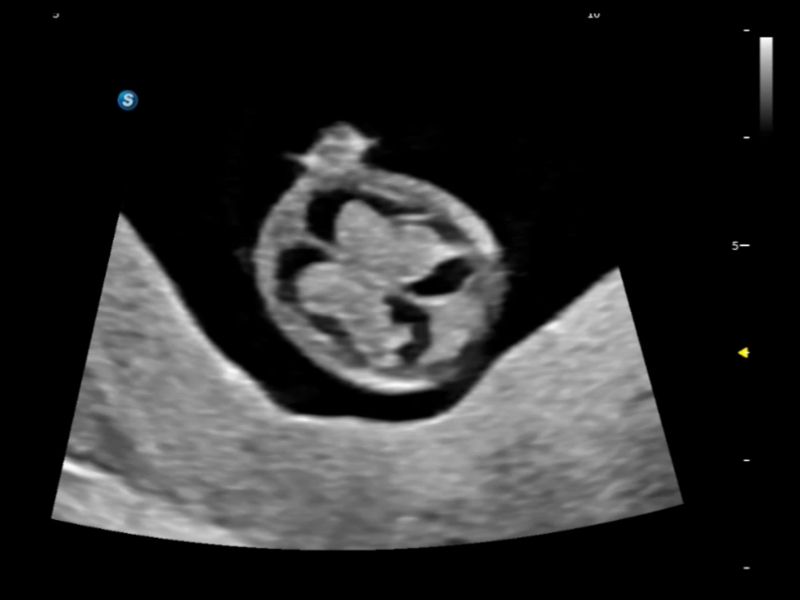

豐富的血流動(dòng)力學(xué)檢測(cè)技術(shù),可在不同醫(yī)療場(chǎng)景中高效捕捉血流信號(hào),助力臨床診療。

在傳統(tǒng)血流的基礎(chǔ)上優(yōu)化掃查和算法策略,能夠更好的抑制組織信息,提煉紅細(xì)胞運(yùn)動(dòng)信息,得到更高幀頻,高靈敏度和分辨率的血流信號(hào),還原更真實(shí)的血流動(dòng)力學(xué)。

通過(guò)光照模型,使二維血流顯示出立體的效果,增加血流的敏感性、成束性,減少外溢??梢院推渌煌难骷夹g(shù)聯(lián)合使用,融合不同技術(shù)的優(yōu)勢(shì)。輕松應(yīng)對(duì)微小血管,增強(qiáng)血流的立體效果,提升視覺(jué)敏感性。

通過(guò)創(chuàng)新的Matrix E自適應(yīng)濾波算法,能有效濾除軟組織和噪聲信號(hào),最大限度保留超低速微細(xì)血流的信號(hào);結(jié)合超長(zhǎng)時(shí)間域算法,極大提升細(xì)微血流的敏感性和空間分辨率,更真實(shí)的反應(yīng)組織、包塊的血流灌注情況。